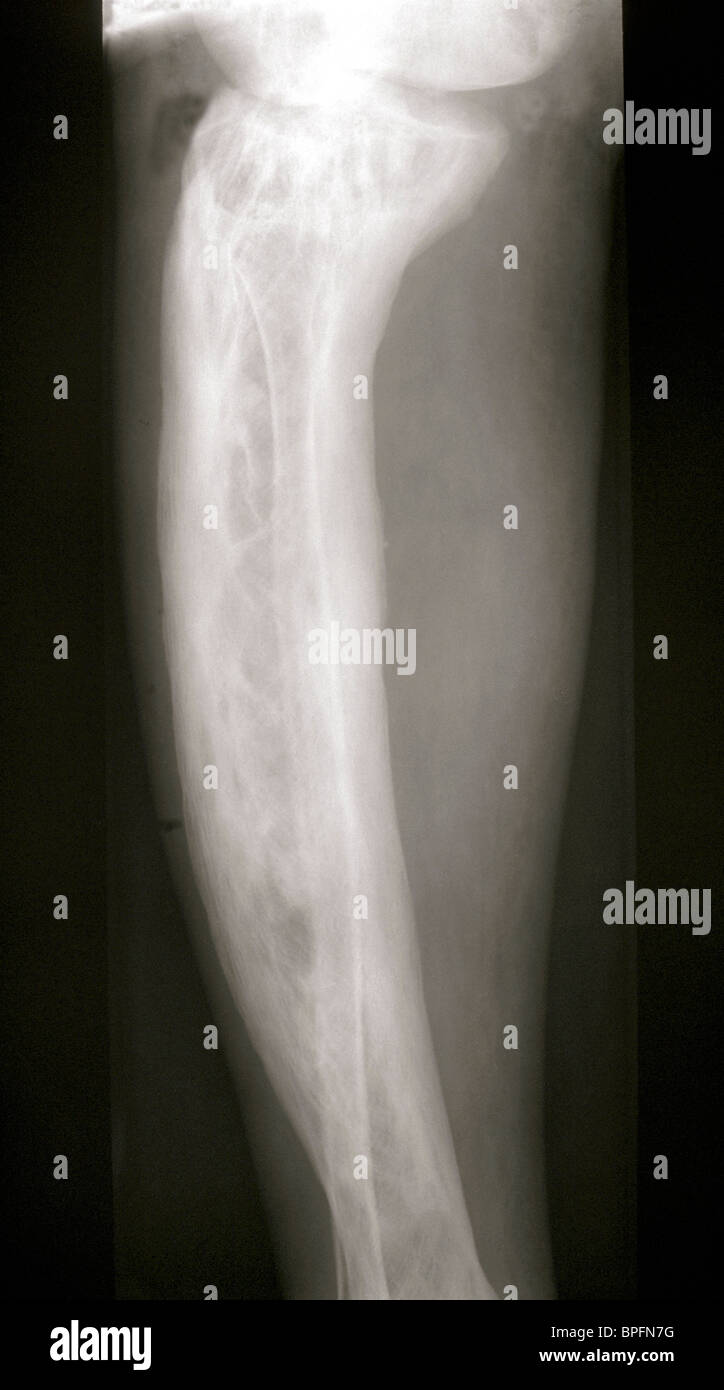

Paget's disease. The radiograph reveals cortical thickening and bone... Download Scientific Paget's Disease Tibia Ask your doctor for advice on preventing falls. However, your pelvis, skull, spine and leg bones (femur. paget disease of the bone is a common, chronic metabolic bone disorder characterized by excessive abnormal bone remodeling. In healthy bone, a process called remodeling removes old pieces of. any of your bones can be affected by paget’s disease. paget. Paget's Disease Tibia.

XRay showing Paget's disease of the tibia bone Stock Photo Alamy Paget's Disease Tibia In healthy bone, a process called remodeling removes old pieces of. paget disease of bone is a benign disorder characterized by focal areas of increased bone turnover in one or more skeletal sites. paget disease of the bone is a common, chronic metabolic bone disorder characterized by excessive abnormal bone remodeling. paget's disease of the bone is. Paget's Disease Tibia.